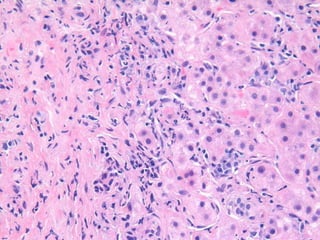

BS09-22346 49 yo, female.  Clinical history:  Acute hepatitis.  Mild elevation of IgG, ANA.  Viral serologies negative.  No drug/toxin exposure history.  AIH?

BS09-10453:  Dx: Chronic hepatitis, with severe activity (perivenular confluent necrosis) and focal fibrous septa, compatible with autoimmune hepatitis. Corresponds to: Modified Ishak stage 2/4 Metavir F2

BS09-22346 49 yo,female. Clinical history: Acute hepatitis. Mild elevation of IgG, ANA. Viral serologies negative. No drug/toxin exposure history. AIH?

BS09-10453: Dx:Chronic hepatitis, with severe activity (perivenular confluent necrosis) and focal fibrous septa, compatible with autoimmune hepatitis. Corresponds to: Modified Ishak stage 2/4 Metavir F2